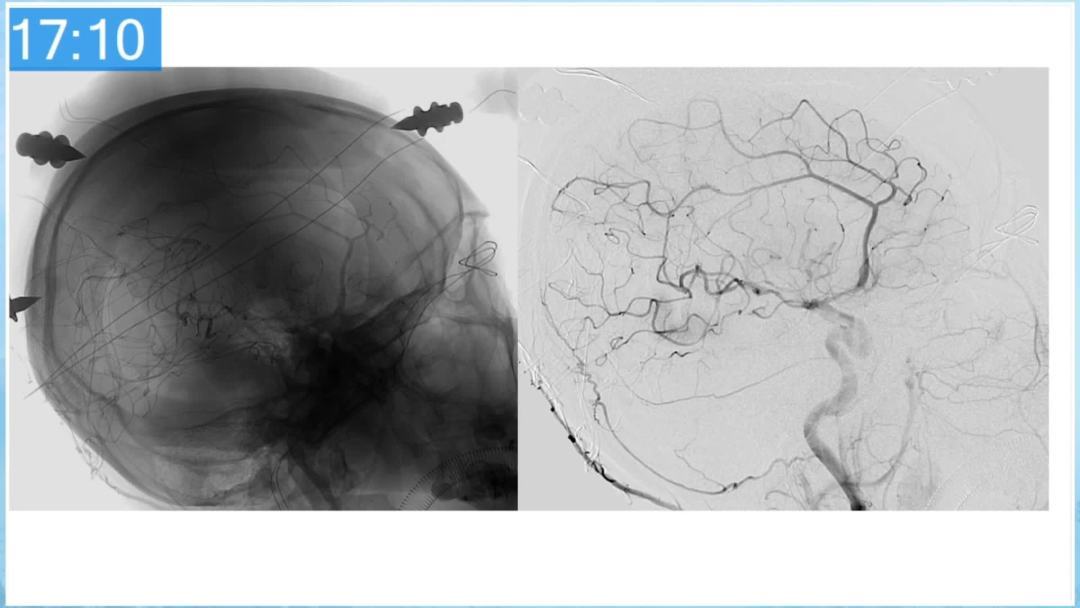

合理的复合平台下的综合治疗,针对每一个病变对应不同方法安全性分析,不预设、不排斥,每种技术发挥到最佳,互相保障。

本期为大家特别分享:空军军医大学唐都医院邓剑平教授的精彩会议内容《颅内动静脉畸形的复合手术治疗》,欢迎大家阅读和分享!